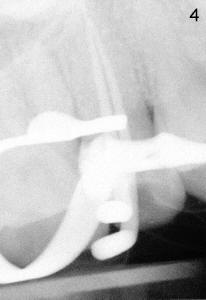

After removing DO caries and enlarging the access, it becomes obvious that there is a missing buccal canal (Fig.3 B). There is purulent discharge from the buccal canal in the beginning of the debridement. Fig.3 photo is taken after the buccal canal is fully shaped with rotary files (final file: 30/.06). Arrowhead points to the original lingual orifice with gutta percha. The RCT retreat is initiated on emergency basis. There is not enough time to remove the lingual gutta percha. More importantly, there is leakage of sodium hypochorite during irrigation due to large DO defect. After drying the buccal canal, the access is sealed with cotton pellet and Cavit. In fact the symptom and signs of reinfection disappear after initiation of RCT retreat. In the 2nd appointment, the occlusal portion of the Cavit is removed for accessing, leaving distal portion in place. The lingual gutta percha is removed and the lingual canal is re-shaped. Fig. 4 shows two master cones (30/.06). The buccal and lingual canals fuse at the apex. Fig.5 photo is taken after the two canals are dried. C stands for the remaining distal portion of the Cavit. There is no leakage during NaHOCl irrigation. Fig.6 shows the final obturation with with possible lateral canal filling (arrowhead). The access is again re-sealed with Cavit (C). Nine days later, the patient returns for prefabricated post and PFM preparation. Finally PFM is cemented. The patient remains asymptomatic.